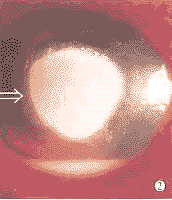

图2 棘阿米巴角膜炎 盘状溃疡合并前房积脓

Fig.2 Acanthamoeba keratitis Disciform ulcer with hypopyon